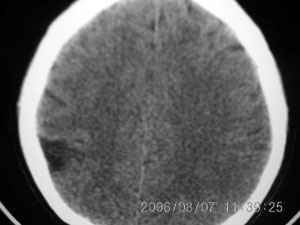

标题: CT4285:头部病变,女 21岁 [打印本页]

标题: CT4285:头部病变,女 21岁

女 21岁 发作性面色发白一年,每次发作仅数秒钟

脑血管畸形,建议做增强

脑软化灶可能性大.

局限性脑软化灶、脑萎缩,考虑动静脉畸形。

建议mri增强检查,不排除dnt可能。

局部软化灶,脑沟增宽加深,考虑为脑血管畸形可能,建议增强或mri检查.

左颞顶叶不规则低迷度影边界尚清楚,岁数年轻,应考虑脑血管畸形。建议强化或核磁,进一步检查。

考虑脑血管畸形可能,建议mr

局限性脑软化灶,右侧侧脑室后角受吸引,略有拉伸。考虑动静脉畸形。

首先考虑avm,但脑囊虫病有没有可能?